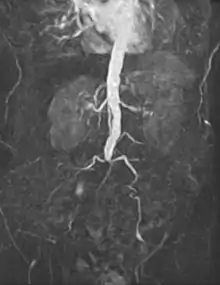

- Abdominal

An abdominal aortic aneurysm (AAA) refers to aneurysmal dilation of the aorta confined to the abdominal cavity. Most commonly, aneurysms are asymptomatic and located in the infrarenal position. Often, they are discovered incidentally or on screening exams in patients with risk factors such as a history of smoking. Patients with aneurysms which have a diameter less than 5 cm are at <1% rupture risk per year. When the aneurysm meets size criteria it can be treated with aortic replacement or EVAR.

- Abdominal aortic aneurysms can be classified as infrarenal, juxtarenal, pararenal or suprarenal as depicted in the illustration.